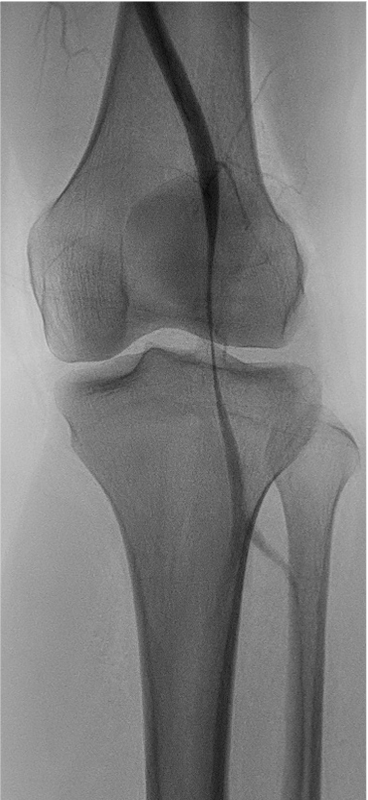

Popliteal entrapment syndrome is a rare condition in which the popliteal artery, which supplies blood to the lower leg and foot, is compressed or squeezed by nearby structures, such as the muscles and tendons at the back of the knee. This can cause reduced blood flow to the lower leg and foot, leading to pain, numbness, weakness, and other symptoms. It is most commonly seen in young athletes and can be treated with surgery or other interventions aimed at relieving the compression of the artery.